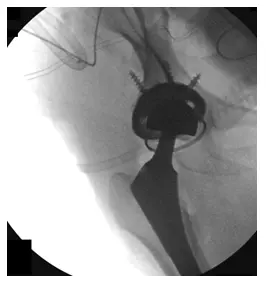

El paciente es un varón de 55 años que acudió a nosotros quejándose de luxación recurrente de prótesis de cadera derecha. El paciente declaró que esto había estado ocurriendo desde que tuvo una artroplastia total de cadera derecha (THA) hace unos años realizada en una...